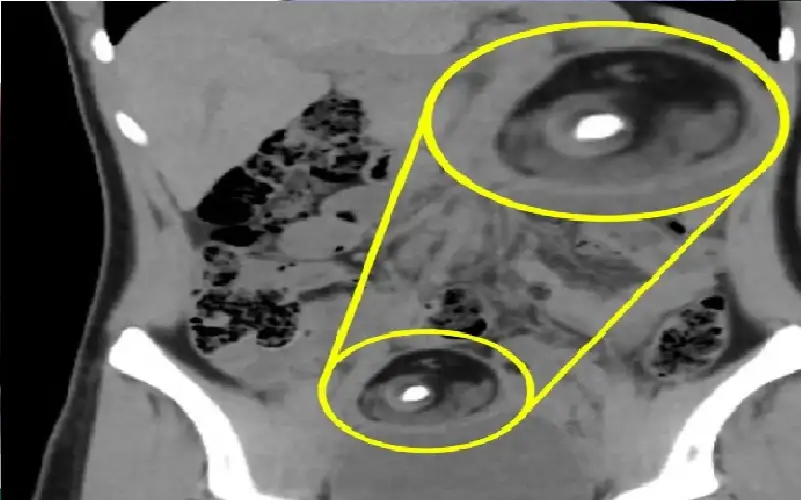

مضاعفات خطيرة لارتفاع مستوى ضغط الدم